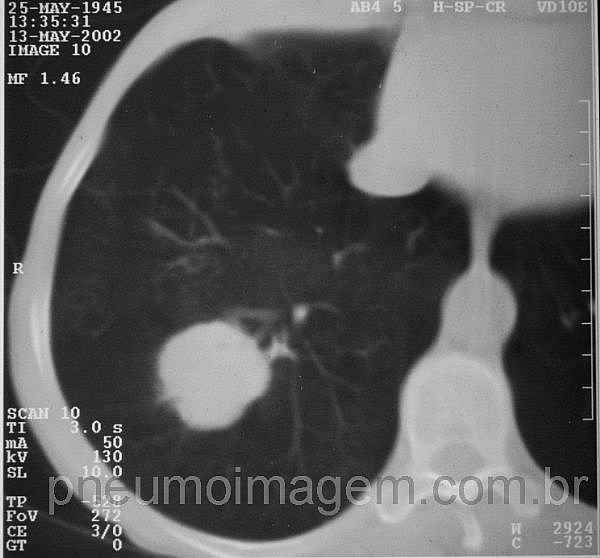

Veja imagens de câncer de pulmão NSCLC no pneumoimagem, clique aqui.